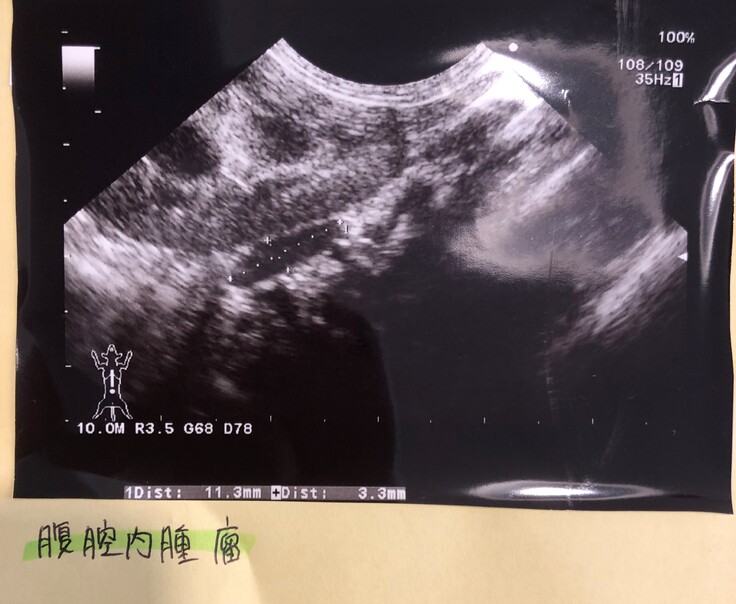

シラスは猫伝染性腹膜炎(FIP)の疑いで、FIPの治療薬を投薬していますが、FIPと断定はされていません。なぜなら、確定診断のための細胞検査で、腹腔内の肉芽(エコー画像を下記に掲載します)の採取が必要とされましたが、腎臓に隣接しており針の刺しどころによっては死亡リスクのある検査になってしまうとのことで、実施できなかったからです。

■腎臓横の肉芽のエコー

※腎臓に隣接した場所に肉芽があります。

針で細胞を採取するのは、リスクが高いとのことでした。